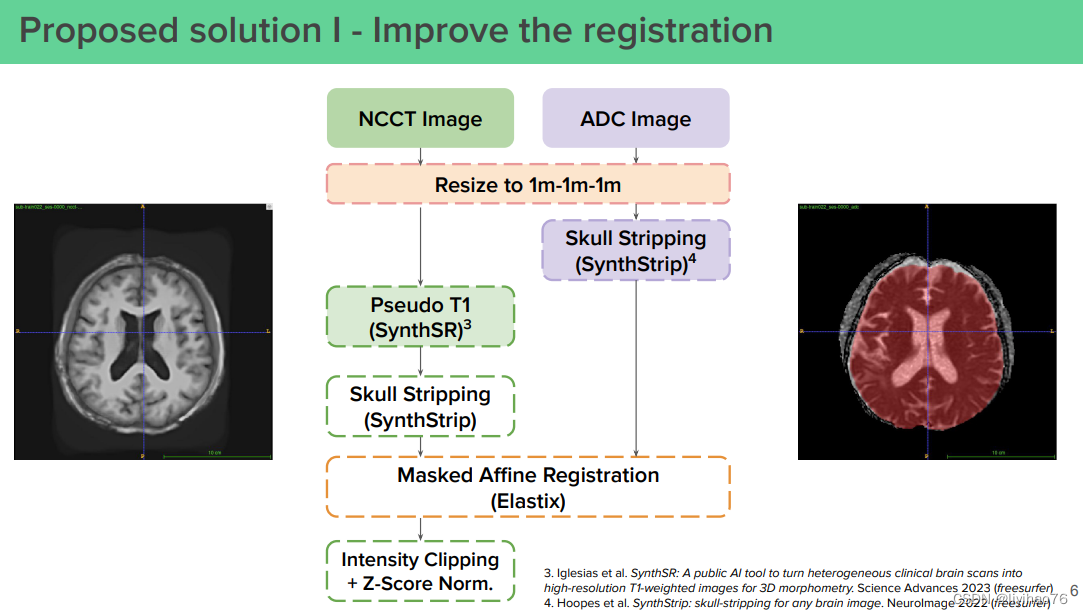

(0) 优化配准